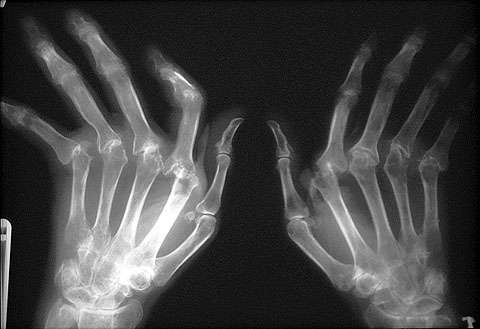

Około 40% ludzi dotkniętych jest chorobą zwyrodnieniową stawów, przynajmniej jednej ręki.

Okazało się, że kobiety były bardziej narażone na chorobę zwyrodnieniową stawów, występowała ona u 47, 2% kobiet i 24,6% mężczyzn. Dolegliwość ta jest częstsza wśród białej populacji – 41,4%, niż wśród czarnej – 29,2%. Większe ryzyko choroby zwyrodnieniowej stawów wiązał się także z nadwagą – 47,1%, w porównaniu do 36,1% występowania u osób bez nadwagi.